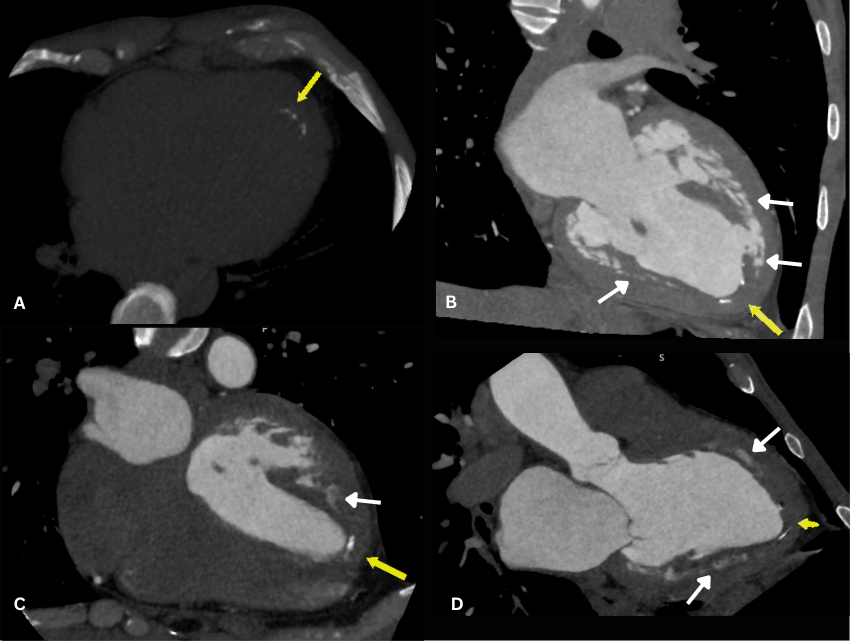

Late gadolinium enhancement sequences. Extensive, dense LGE in the LV apex, mid inferior, and inferolateral segments with a characteristic "V-shaped" morphology - Yellow arrows; Subendocardial LGE in the inflow tract and papillary muscles - Pink arrow; LGE in the right ventricular apex - Blue arrow; A non-enhancing apical mural thrombus - White arrows..png)